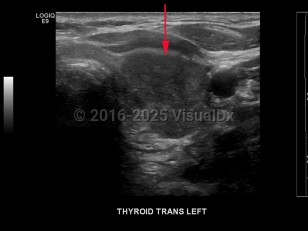

Signs and symptoms include a neck lump or swelling, neck pain, hoarseness, dysphagia, dyspnea, and/or persistent cough. Erythroderma may rarely be a cutaneous manifestation of malignancy.

- Anaplastic thyroid cancer – A poorly differentiated and aggressive form of thyroid cancer. Most patients die within 6 months of diagnosis.

- Medullary thyroid cancer – This can either be sporadic or familial as part of multiple endocrine neoplasia type 2A (MEN2A), type 2B (MEN2B), or medullary thyroid cancer without other features of MEN. Surgical resection is the preferred method of treatment, with elevated calcitonin levels post-surgery indicating residual disease.